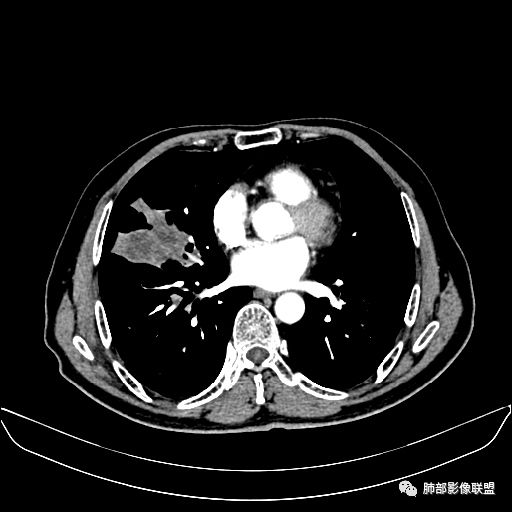

动脉期

静脉期

老年男性,因“咳嗽咳痰1月余。”入院。病程中咳嗽咳痰,咳黄白痰,间断咯少许鲜红色痰血。PPD阳性。胸CT:右肺中叶外侧段支气管管腔阻塞,大片实性病变,病灶边缘光滑,部分边缘膨隆,可见分叶,肺门及纵隔可见肿大淋巴结,并可见钙化。增强可见病灶明显强化,而且延迟强化明显,病灶内多发低密度区,内见血管影,血管变细、部分血管破坏。考虑恶性病变可能性大,鉴别慢性肉芽肿性病变。

胸CT:跨叶大肿块,主体在中叶,右中叶外侧段支气管阻塞,病灶部分边缘膨隆,可见分叶,部分边缘平直,肺门及纵隔可见肿大淋巴结。增强病灶不均匀强化,延迟强化明显,病灶内多发低密度区,内见血管飘浮,部分血管变细、模糊。考虑:恶性病变可能性大,大细胞?淋巴瘤?鉴别慢性肉芽肿性病变。

吴婧老师和南边老师都对该病例进行了深入分析。从支气管管壁的增厚,支气管狭窄后扩张,支气管粘液栓,病灶形态,到病灶不均匀强化及坏死彻底,到周边病灶及肺组织空气的潴留,加之纵隔内淋巴结肿大伴钙化等等,都支持慢性炎性病灶,尤其是结核。

墨西哥仙人掌征---结核        影像上结核灶,粗大的均匀枝干,推测是支气管囊状扩张引起的,在非支气管区,形成圆形坏死囊群;如果这些坏死比较稀薄,又遇到扩张支气管,就会形成粗大的“墨西哥仙人掌”。结核引起的支气管近端炎症纤维化,可以造成支气管阻塞,从而将干酪样坏死物封堵在管腔内。仙人掌主干内部应该是干酪为主,稀薄的,具有流动性,时间久了会出现钙化。